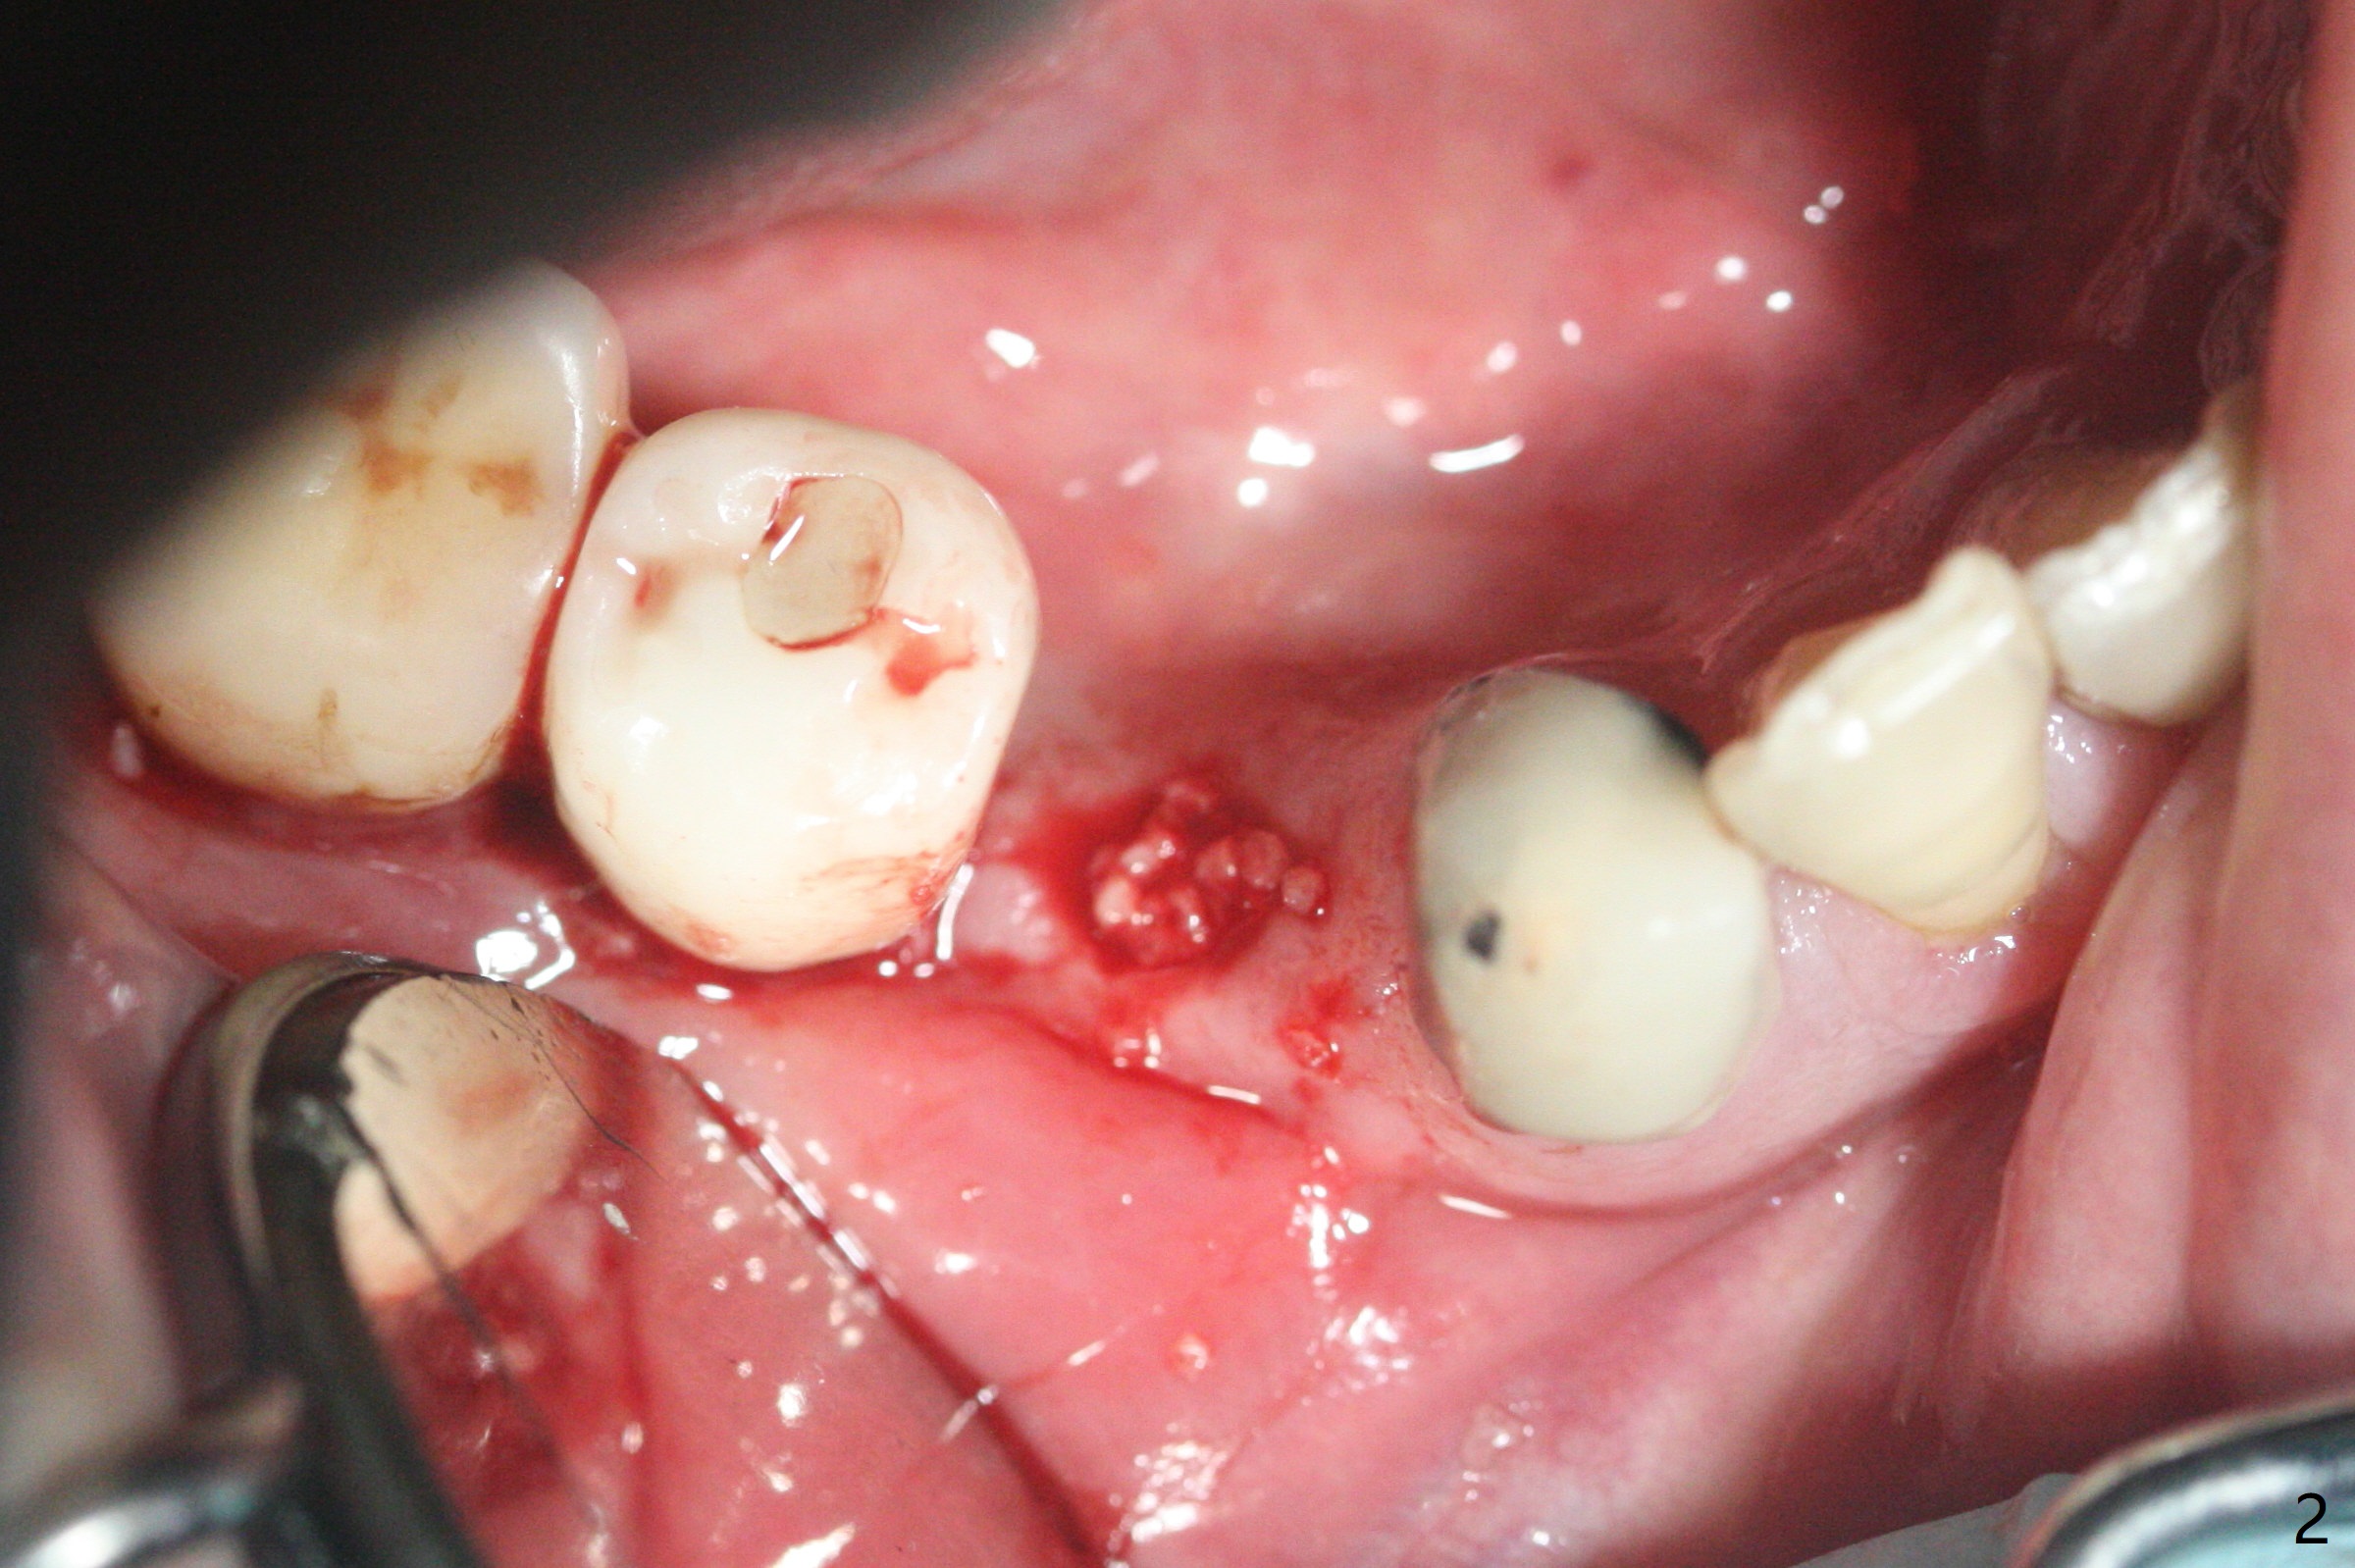

52岁男右下4植体脱落三天回到诊所(图一),植牙创尚未闭锁,顺着开口去除肉芽组织,冲洗,充填皮质骨骨粉(图二,三),颊侧骨板外形恢复(图四,五:*)。重新植入UF植体(5)颊侧还有薄颊侧骨板(图五:>),而6植体周围骨质吸收(图六),植骨好像有希望,植体还在牙槽骨范围,也有利于5植体生存。术后12天伤口愈合(图七)。尽管使用水枪,仍有6植体周围炎,需要治疗(图八)。由于右侧手术,病人不得不用左侧咀嚼,他认为左下4松动,无法挽救。术后3.5个月牙槽嵴和角化龈缩小(图九),需要切开使用导板。术后3.5个月骨粉高度明显下降(图十)。只能植入4x8.5毫米植体(图十一)。